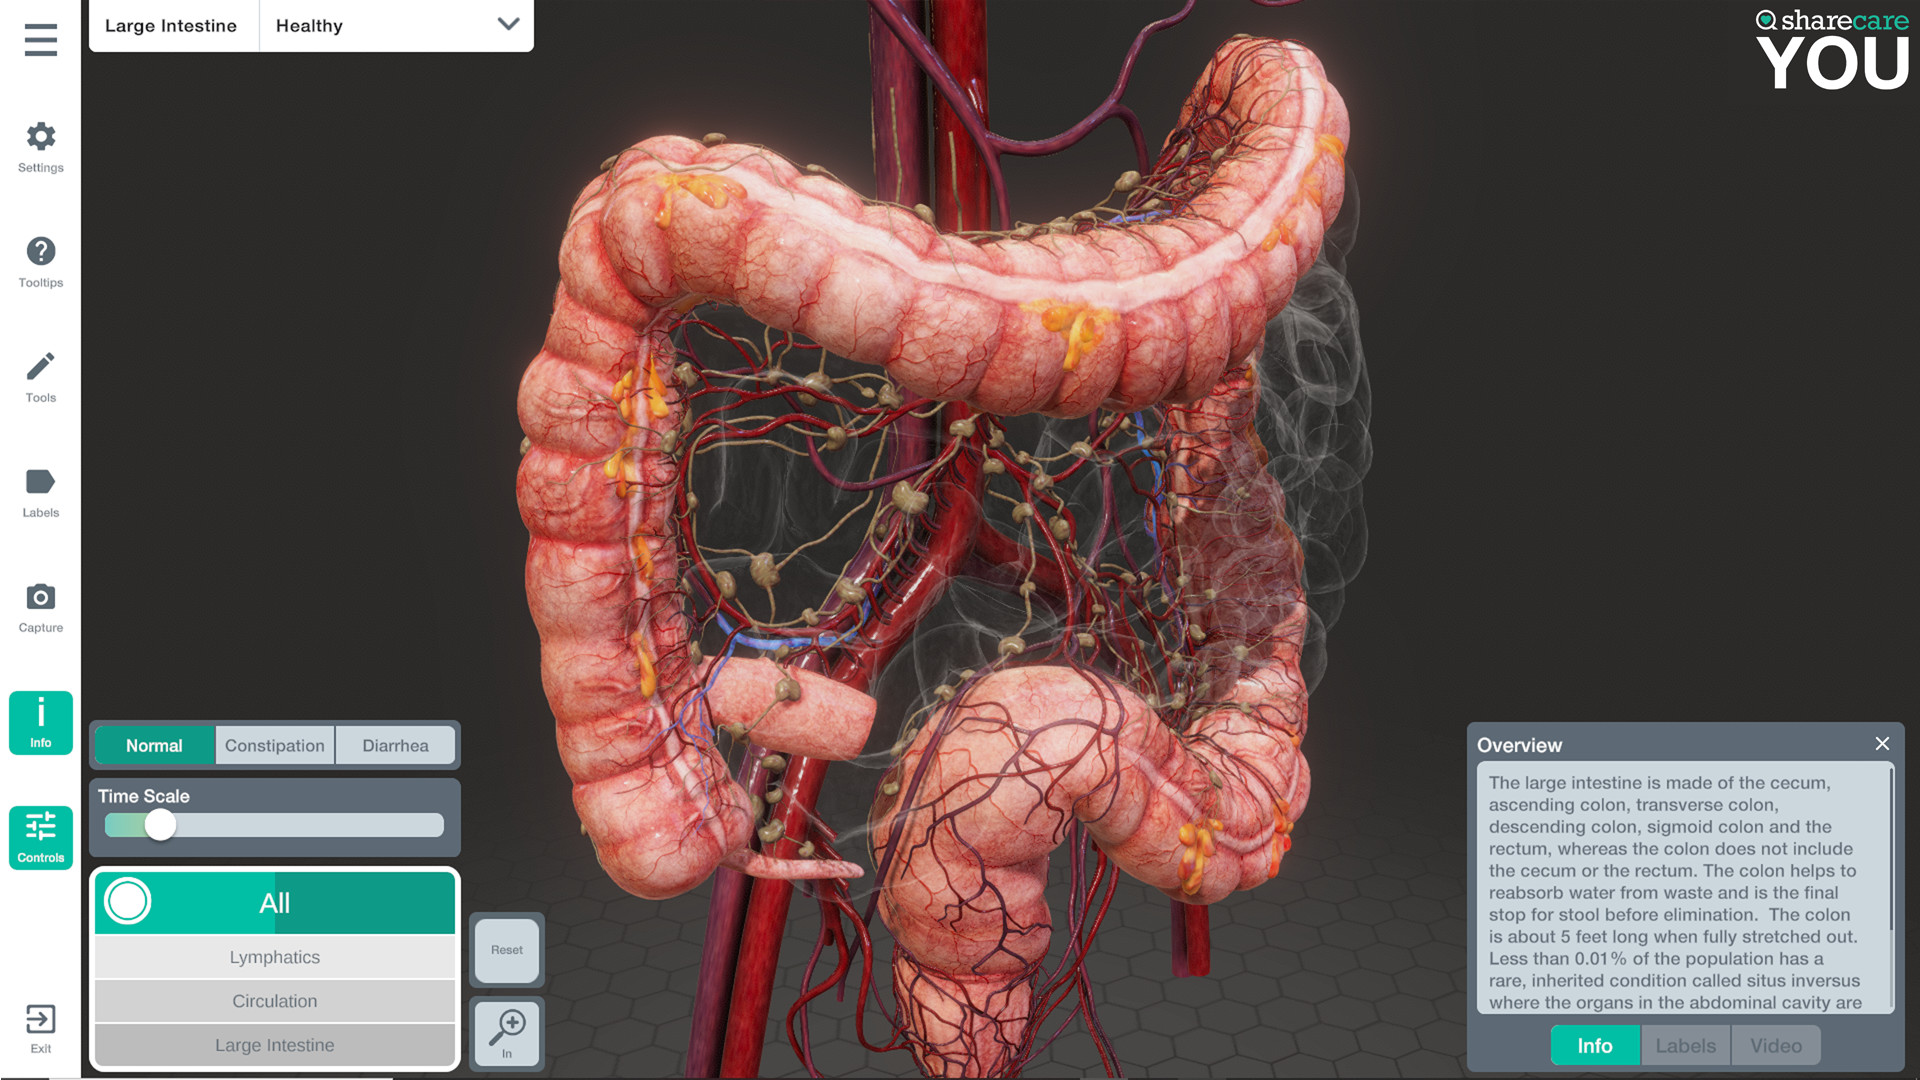

Sharecare YOU是一种完全身临其境的、逼真的人体模拟,让任何人都可以 360 度全方位探索其惊人的细节。

有兴趣了解特定器官吗?只需单击一个按钮,即可进入内部,想象其自然功能,并深入探索。想了解更多吗?查看沿途的许多标签和标签,以获得更多信息和洞察力。轻松定制您以更好地了解生理学和模拟疾病。您甚至可以将我们的头像个性化为虚拟的您——您的健康、您的状况。这真的是关于你的。

- 你的内容 – 一个包含 40 多个不同场景的扩展库供探索,包括解剖学、生理学、条件和治疗

- 信息标签和场景信息

- 具有独特交互式控件的完全更新的用户界面